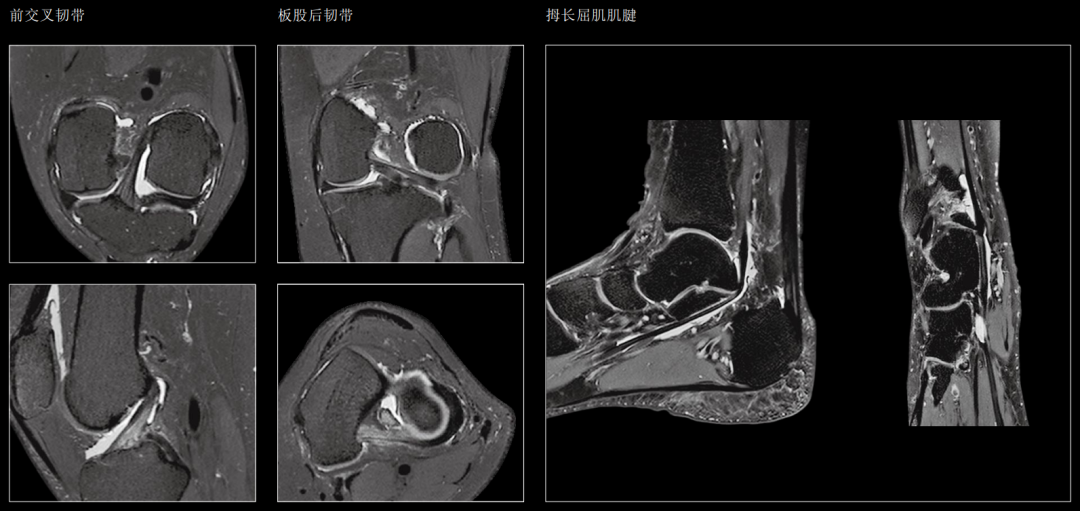

5、骨与关节:

骨内感染、肿瘤、外伤的诊断与病变范围,尤其对一些细微的改变如骨挫伤等有较大价值,关节内软骨、韧带、半月板、滑膜、滑液囊等病变及骨髓病变有较高诊断价值。

骨关节成像